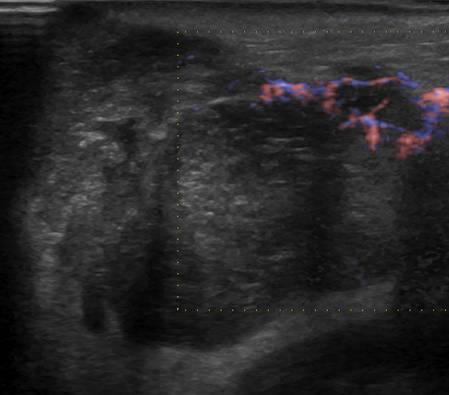

U tuyến nước bọt

» Thông tin: Nam giới – 79 tuổi.

» Lâm sàng: Khối vùng mang tai / K thực quản.

# Di căn tuyến nước bọt mang tai.